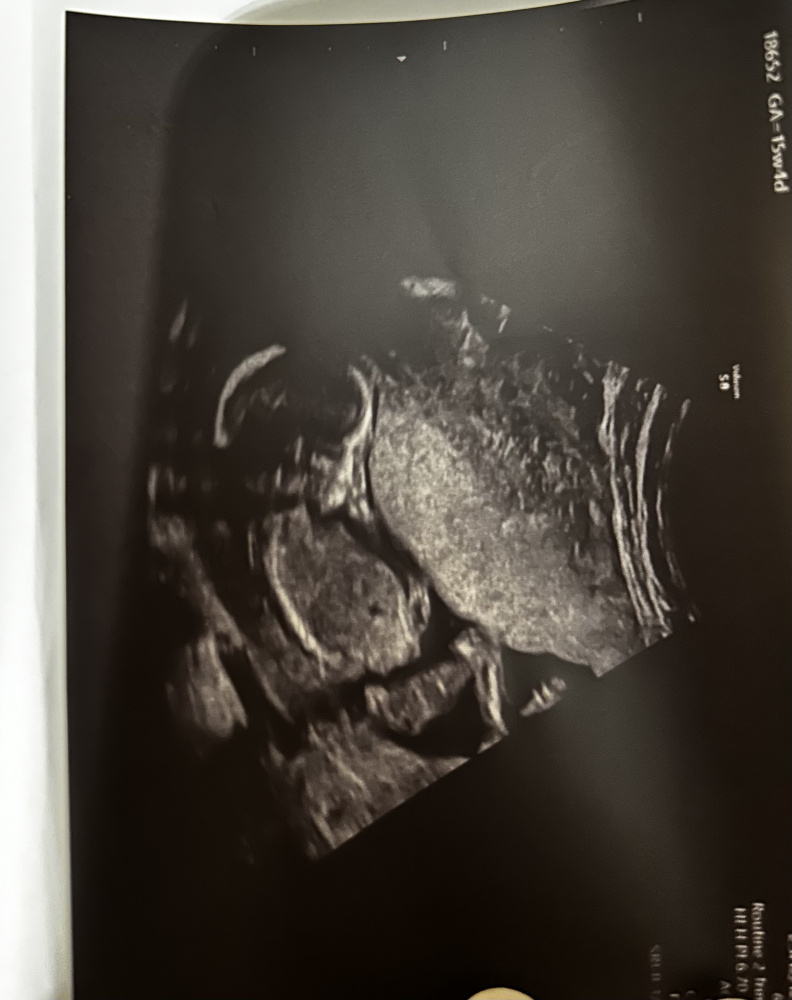

Ultraschall von oben - 2 Striche Mädel oder Bub?

Hallo Zusammen, das Bild ist in der 12. SSW entstanden. Man schaut von oben auf unseren Krümel. Es sind zwei sehr deutliche Striche. Jemand Erfahrung ob dies eher Mädchen oder Junge ist?